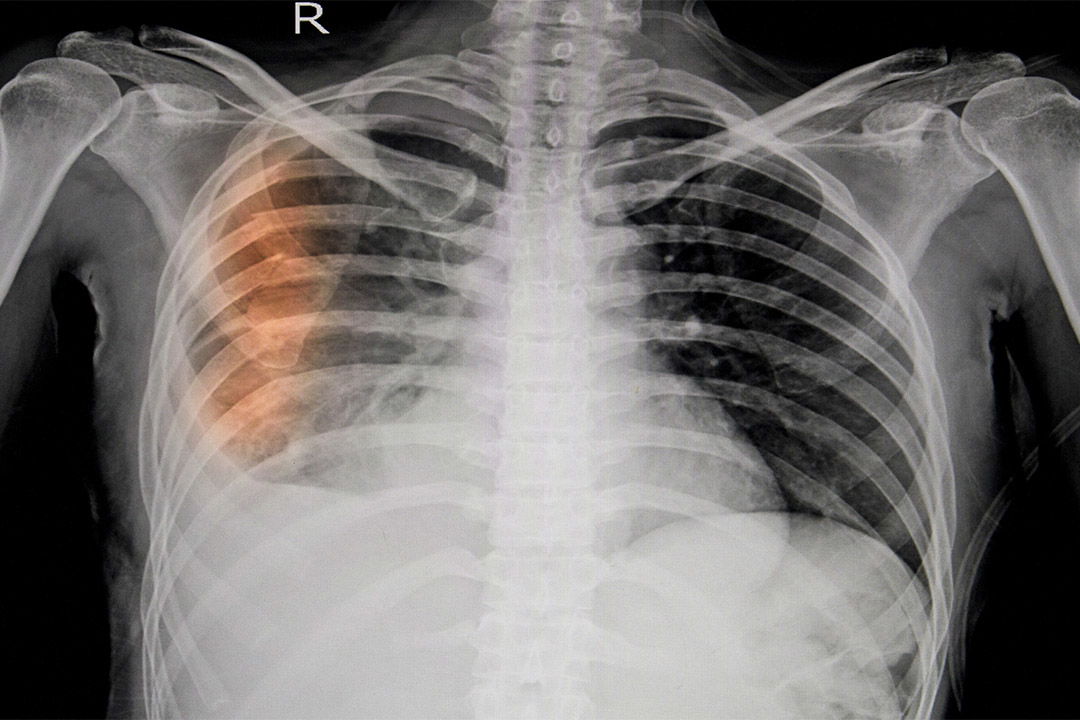

Ob es sich um eine Prellung oder einen Bruch handelt, lässt sich manchmal nicht auf den ersten Blick unterscheiden Bei der geprellten Rippe (Rippenkontusion) ist die Rippe und/oder das umliegende Gewebe beschädigt Selbsttest: Rippenprellung oder Rippenbruch? Ob Sie sich einen Rippenbruch zu gezogen habe oder Sie sich die Rippen nur etwas geprellt haben, kann in der Behandlung eine sehr große Rolle spielen

Gebrochene Rippe Was Tun Cohomemade. Fahrrad-, Reit- oder Skiunfälle, Stöße oder Stauchungen bei Autounfällen oder auch die klassische Haushalts-Panne, die mit einem Sturz oder einem Stolpern gegen Möbelkanten oder Treppenstufen endet: Alle diese Situationen können sowohl Prellungen als auch eine Rippenfraktur auslösen Eine eindeutige Diagnose kann nur durch Fachpersonal gestellt werden.